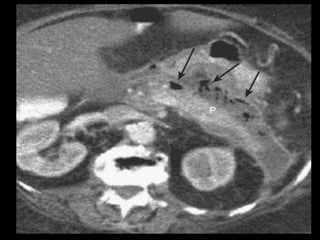

Coleções líquidas agudas- TC

Hipodensas

Mal definidas

Sem cápsula ou parede reconhecível

Resolução espontânea em 50% dos casos;

Complicações: dor, infecção secundária e

hemorragia;

São passíveis de drenagem percutânea caso não

regridam ou se tornem infectadas.